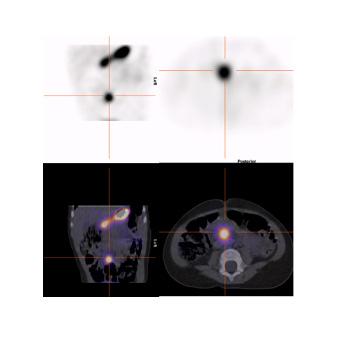

La scintigraphie au Pertechnétate de Tc99m est le test de choix pour identifier la muqueuse gastrique ectopique chez les patients dont la suspicion clinique est élevée. Cependant, quoique le diverticule puisse potentiellement être identifié sur la TDM faible dose si effectuée, s’il n’y pas de muqueuse gastrique ectopique ou cause de faux positif, l’étude scintigraphique par elle-même sera négative. Dans la scintigraphie au 99mTc-Pertechnétate, la captation du traceur est principalement au niveau des cellules sécrétrices de mucine mais son élimination est influencée par les cellules pariétales11,12. Sans manipulation pharmacologique, il y a élution du traceur de l’estomac vers le duodénum et le grêle en cours d’étude. Il est également visualisé l’élimination physiologique par les reins vers la vessie (figure 1 ).

Figure 1 : Examen effectué sans préparation pharmacologique et avec SPECT simple chez un patient de 4 ans avec rectorragies. Mise en évidence d’une élution du traceur en cours d’étude avec visualisation du duodénum et du grêle. Acquisition dynamique ( A ), cliché statique à 30 minutes post injection (B) et rendu 3D de l’acquisition tomographique (C)